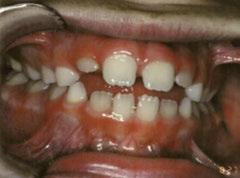

Figures 1A and 1B: Adolescent with anterior open bite: Orthognathic surgery unnecessary post-myofunctional therapy. 1A. Pre-myofunctional therapy: The bite only touched on the back molars, yet the patient had already gone through full braces. The original orthodontist recommended orthognathic surgery to close the bite. The patient was referred for a second opinion. The second orthodontist recognized the tongue thrust and referred the patient for myofunctional therapy but made no guarantees that the patient would not need jaw surgery. 1B. Post-myofunctional therapy: After 2.5 years of braces and myofunctional therapy, the orthodontist gave the patient the good news that jaw surgery would not be necessary. The myofunctional therapy allowed the orthodontist to close the bite once the tongue pressure was removed from between the teeth

B.

A.

Figures 2A and 2B: Open bite corrected with myofunctional therapy. 2A. Pre-myofunctional therapy: This patient was in braces for 3 years with no success at closing the open bite. 2B. Post-myofunctional therapy: After 5 months of myofunctional therapy to address the mouth breathing and tongue thrust, the open bite closed

Figures 3A and 3B: 3A. Pre-myofunctional therapy: Anterior open bite caused of soft tissue dysfunction including incorrect lingual rest posture and tongue thrust. 3B. Post-myofunctional therapy: 4 years after the start of myofunctional therapy with no orthodontic treatment, and the open bite closed. By taking the tongue pressure off of the teeth in OMT, the occlusion was able to normalize. The orthodontist feels the patient does not need braces

Figures 4A and 4B: Unilateral open bite developed later in life. 4A. This patient’s unilateral open bite was due to a change in muscle function, as after a left root canal, the patient began to only chew on the right side. This chewing pattern changed the muscle balance as the patient continually spread the right side of the tongue to push food onto the teeth. There was no orthodontic progress, and the patient was referred for orofacial myofunctional therapy. 4B. OMT restored muscle development, resting tongue posture, correct chewing function, and correct swallowing. In 5 months, the patient was debanded